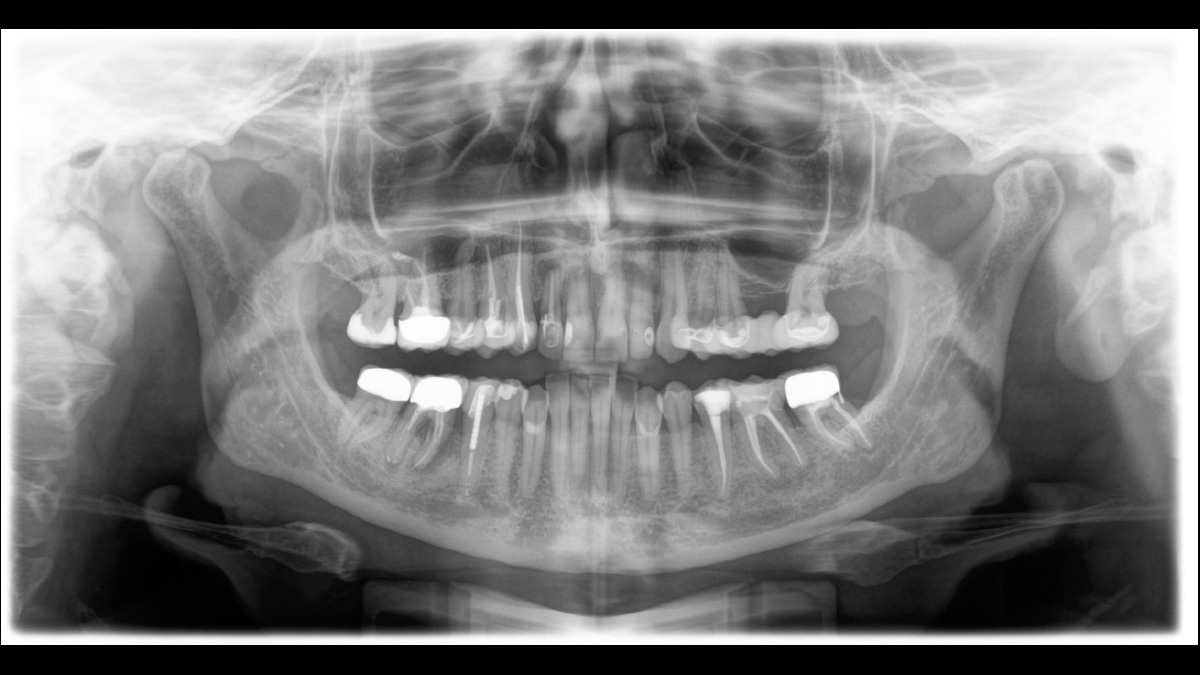

Für hervorragende Panorama-Röntgenaufnahmen ist der richtige Fokus entscheidend. Mit der Autofokusfunktion erhalten Sie automatisch ein Bild mit der bestmöglichen Schärfe im Fokus. Dentsply Sirona Röntgengeräte erstellen in einem Umlauf mehrere tausend Einzelaufnahmen und erkennen vollautomatisch die Bereiche, in denen der Kiefer optimal in der scharfen Schicht liegt. Ohne zusätzliche manuelle Schritte werden diese Bilder dann in einem Gesamtbild mit maximaler Zeichenschärfe dargestellt.

Einige Teile des Bildes sind scharf, andere Bereiche bleiben unscharf.

Das System erkennt in einem Umlauf die relevanten Bereiche aus mehreren tausend Einzelbildern und identifiziert automatisch die Bereiche, in denen der Kiefer optimal in der scharfen Schicht liegt.

Zeichenscharfe Bilder.